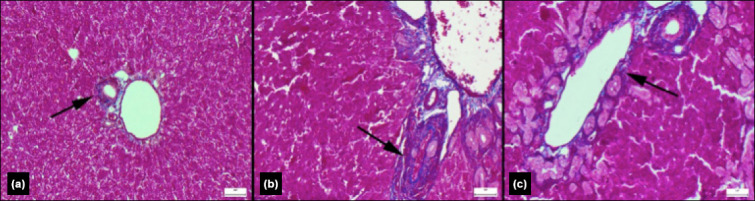

Results: Biochemical analysis showed significantly elevated levels of liver and biliary injury markers, including aspartate aminotransferase (AST), alanine aminotransferase (ALT), alkaline phosphatase (ALP), and gamma-glutamyl transferase (GGT), in the OJ group. These markers were significantly reduced in the RO group. Additionally, oxidative stress markers such as malondialdehyde (MDA) and myeloperoxidase (MPO) were lower in the RO group compared to the OJ group. Although levels of antioxidant enzymes, including glutathione peroxidase (GSH-Px) and superoxide dismutase (SOD), were higher in the RO group, the differences were not statistically significant. Interestingly, C-reactive protein (CRP) levels were unexpectedly higher in the RO group than in the OJ group, possibly due to the study duration or dosing protocol. Histopathological examination revealed significant portal inflammation, bile duct proliferation, polymorphonuclear leukocyte (PMNL) infiltration, necrosis, and fibrosis in the OJ group. Conversely, the RO group showed substantial reductions in these pathological features, including milder bile duct proliferation and necrosis (p<0.001). Additionally, connective tissue expansion and collagen deposition were significantly lower in the RO group compared to the OJ group.